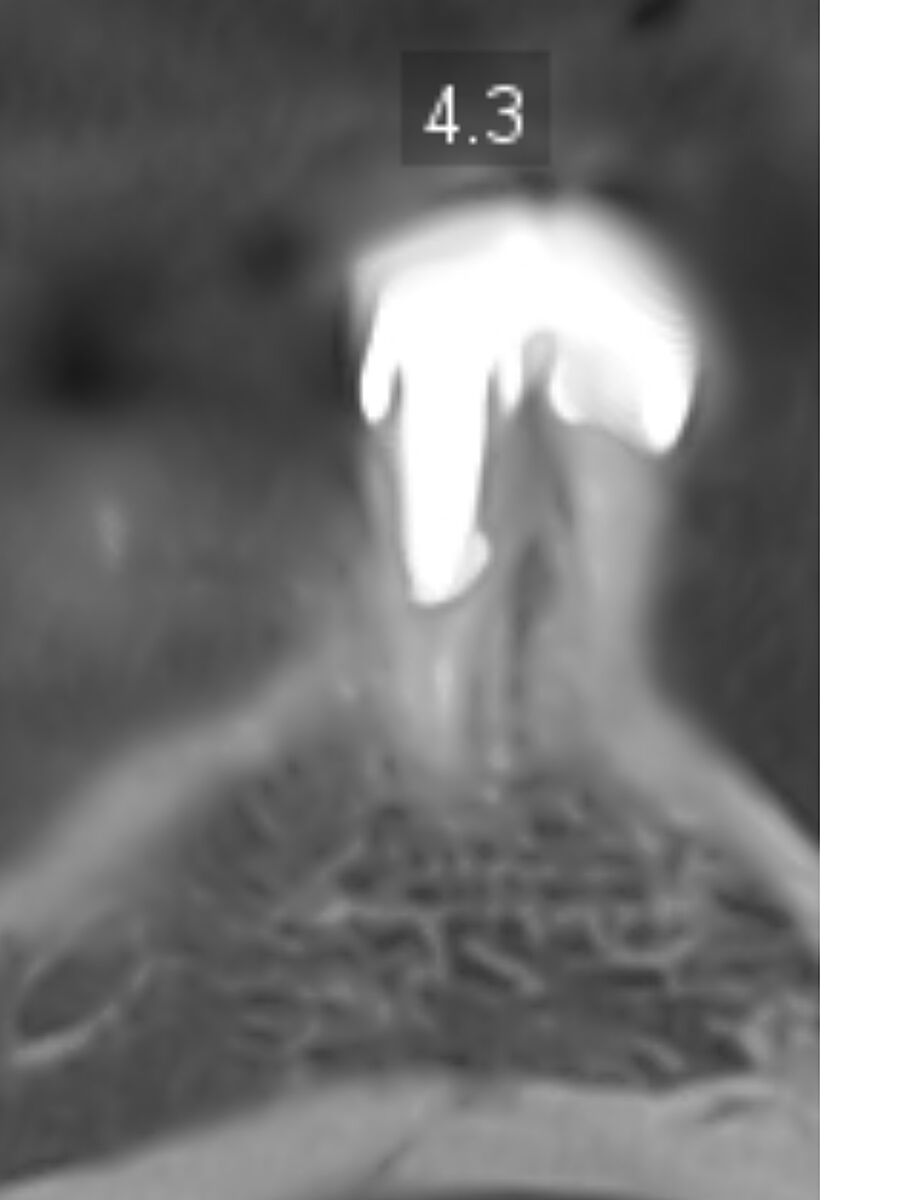

В 70 років приживуться імпланти? Ви суму можете уявити. На знімках канали і корені зубів нормальні, проліковані. Запалень нема. Простіше поміняти старі коронки і поставити незйомні мости на імпланти. По два на одну сторону. Або в такому віці можна дешевий протез, що до ясен прилипає, типу резиновий. Кожні два роки міняти.

Хоч і на штифтах, але корені нормальні, коронка зуба проглядується. У вас навіть прикус правильний при відсутності бокових зубів зверху і знизу. Відстань між щелепами де пусті місця по боках прям ідеально симетричні і не сильно просіли.

Есть здесь зубы нормальные. Есть под вопросом. Т.к. этот снимок надо смотреть полноценно , а не скрины с него. Здесь могут быть и срезы неудачные, и не всегда понятно - артефакты это или на самом деле это есть. + замеры делать надо. И это только рентгенологически... Иногда составляются планы с удалением относительно нормальных зубов для экономии средств и снижения травматичности операции...